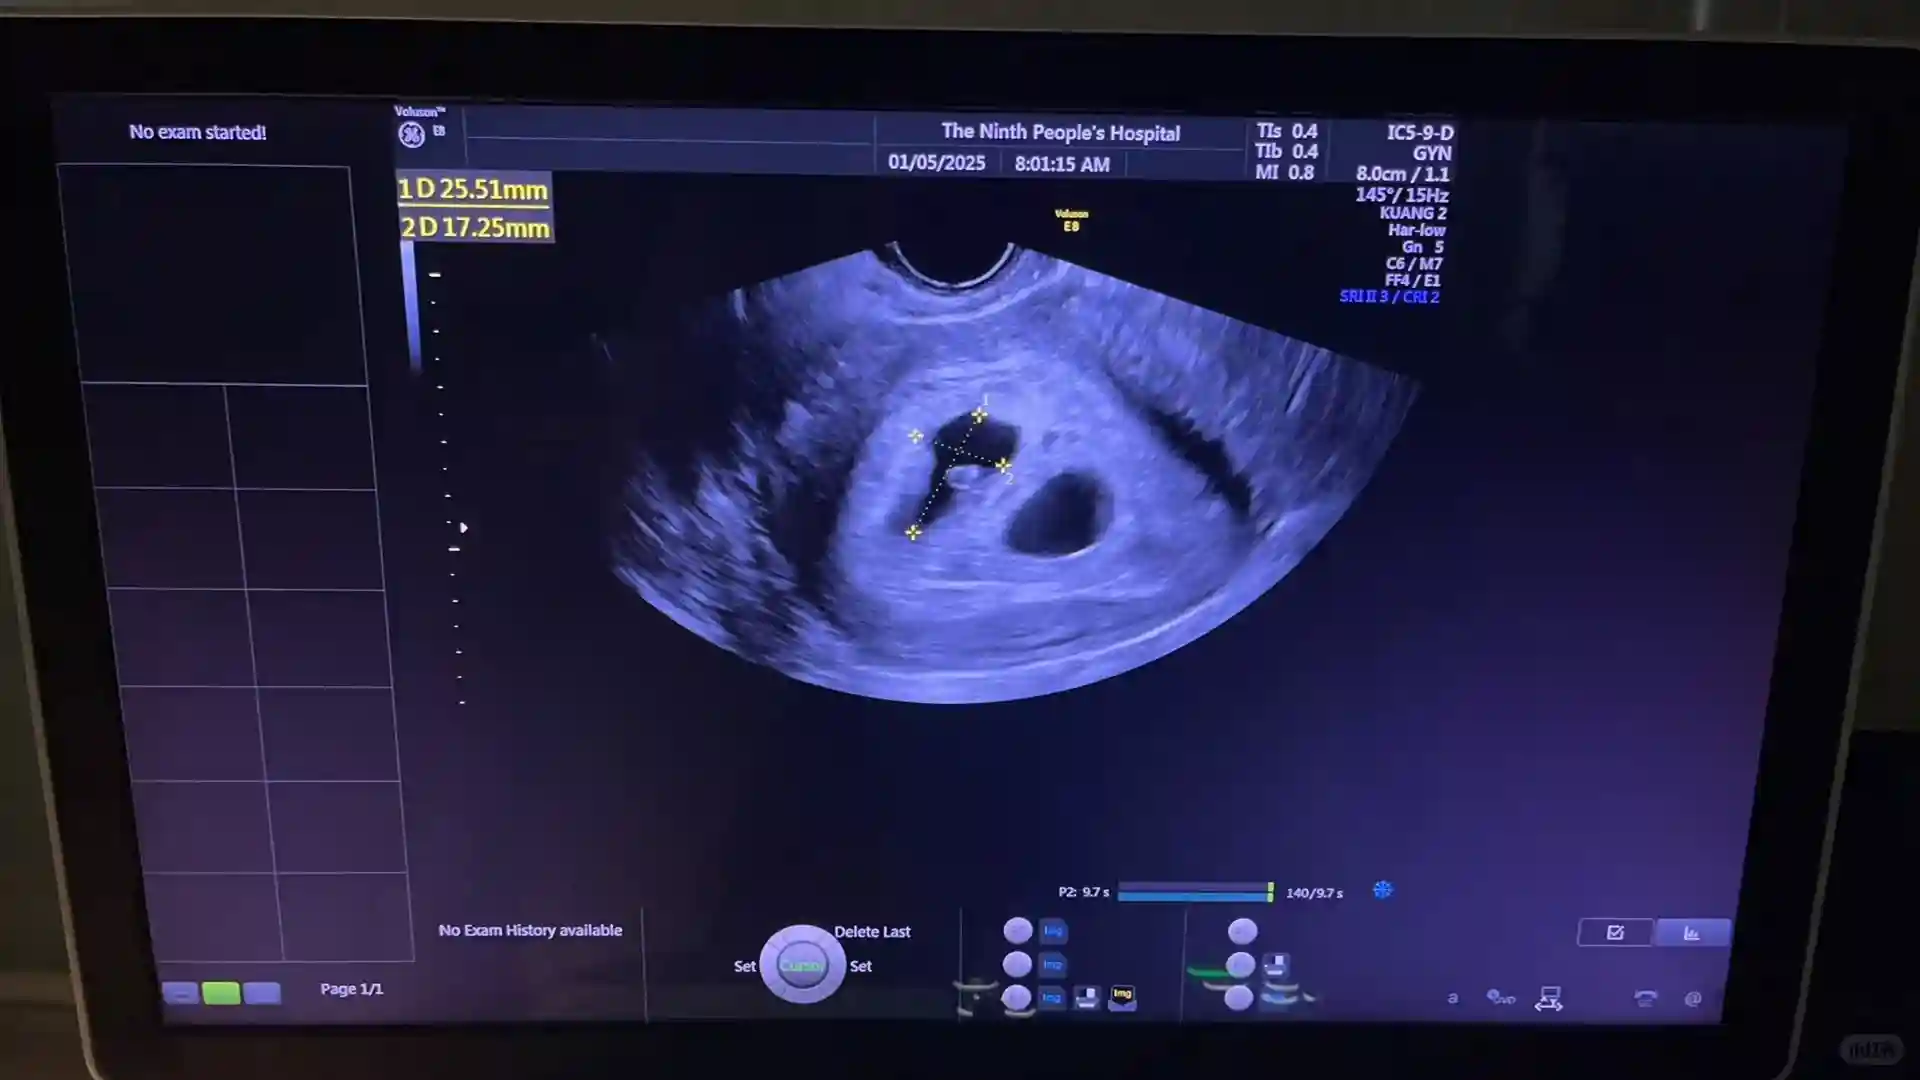

所有的B超检查,取卵,移植都是自己来操作